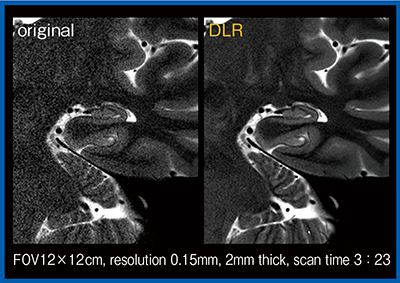

DLRは2Dの撮像にも応用可能である。図6は,FOVを絞って約3分で撮像した海馬の高分解能T2強調画像であるが,DLRを適用することでノイズが大幅に低減し,海馬の内部構造なども明瞭に描出されている。

図6 海馬の高分解能2D-T2強調画像におけるノイズ低減